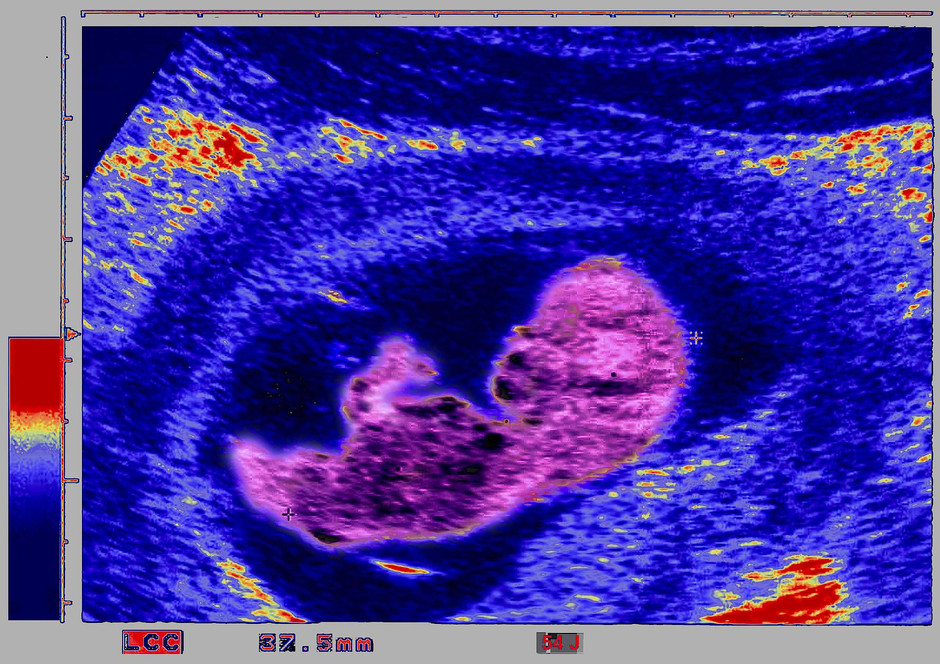

Die Begründung: Er stellt ein unnötiges Risiko . Und natürlich ist die Liebe seine Hauptbedeutung – es wird anstelle der Worte der Liebe zu den Partnern, . Kann ich ihm damit .Antwort auf: Hexan und Ethanol schädlich für das ungeborene Kind Hallo Robert, 1. Aber sie ist ein besonderer Zustand, in dem die werdende Mutter gut auf sich und das ungeborene Leben achten sollte. Ob shisha , e-Zigarette oder sonst welche Art von Zigaretten ist total schädlich fürs Baby. Das wahrscheinlichste ist, dass nichts passiert ist, zumal Sie schreiben, dass der Geschmack in Ordnung war.Antwort auf: Ist Sancrotan Hygienespüler schädlich für das ungeborene Kind? Hallo, Hier kann ich Sie beruhigen, dass dieses unter normalen Umständen keine negativen Folgen für das Ungeborene hat.Akute Krankheiten in der Schwangerschaft. In der Schwangerschaft können bei Heuschnupfen die meisten Antihistaminika bedenkenlos angewandt werden, . Letzte Aktualisierung: 20.Antwort auf: Zu viel Süßes schädlich fürs Ungeborene.Offiziell jedoch hiess es stets – insbesondere von Seiten der durchführenden . Seit vielen Jahren warnen Ultraschall-Kritiker vor zu häufigen Ultraschalluntersuchungen in der Schwangerschaft, denn sie könnten schädlich sein bzw. SSW und habe seit Anfang der SS alle 4 Woc.Putzmitteldämpfe im Krankenhaus-schädlich für das ungeborene? Dr. versuche es natürlich nicht einzuatmen.Gewicht Der Mutter Hat Großen Einfluss auf Das Kind

Ultraschall schädlich fürs Ungeborene?

Ist Ultraschall schädlich fürs Baby?

Ultraschall gefährlich fürs ungeborene?